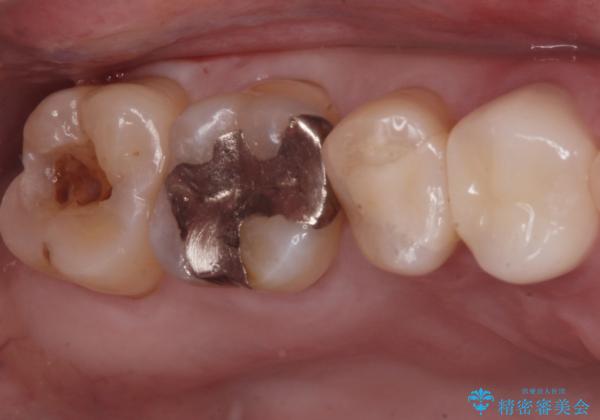

- 奥の歯に穴が空いているとの事で来院。

拡大鏡下で虫歯を全て除去しゴールドインレーにて治療しました。

- ゴールドインレー 7.7万円費用は治療当時の料金となります

ゴールドインレーはメタルインレーに比べて、歯と詰め物の隙間が生じにくため

虫歯菌が侵入することなく、虫歯の再発のリスクが低いです。